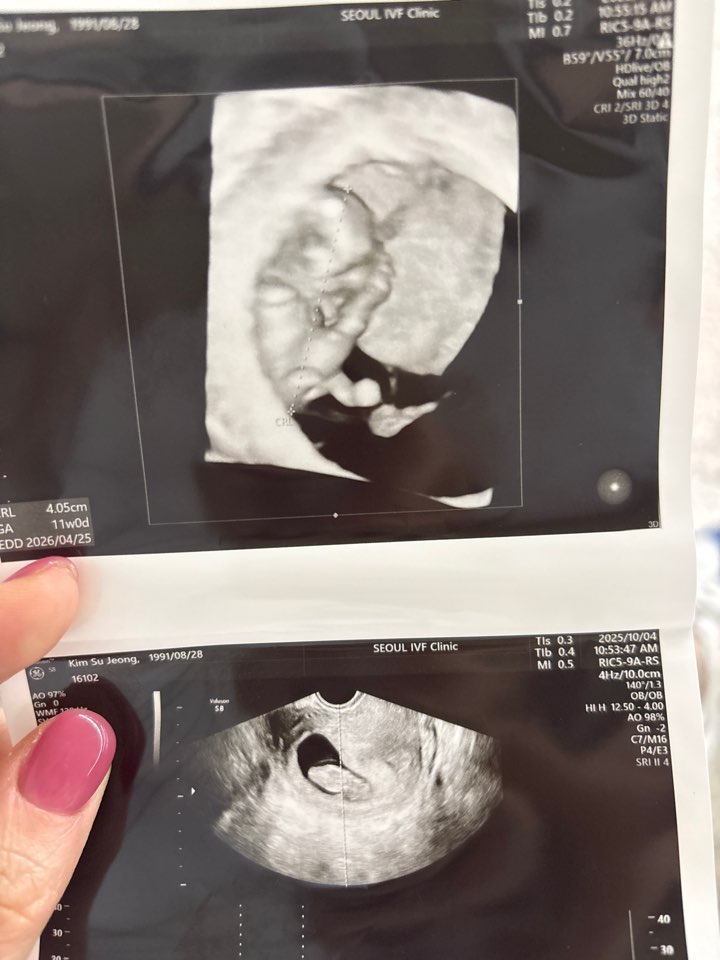

| 가슴 떨리는 임신 이야기를 공유해 주세요. | 채취를 하고 마지막배아가 남았었어요. 신선 동결1차 모두실패하고 마지막 이식날, 제일 마음을 편하게 먹었던 것 같아요. 안되면 다시 채취하면되지~!라는 마음으로 이식을 했고, 이번 이식은 출근도 안하고 집에서 정말 편히 쉬었어요. 5일부터 임테기 두줄을 보고 떨리는 마음으로 피검사를 갔고 좋은 결과를 들었습니다. |

| 치료 도중 느꼈던 가장 기뻤던 순간과 절망적인 것들은 무엇인가요? 잊지 못할 경험이 있나요? | 가장 기뻤던 순간은 난자채취 후 동결배아 3개가 나왔다고 들었을 때, 가장 절망적이었던 순간은 이식 후 임테기에 단호박 한 줄만 떴던 그날이었습니다. |

| 서울IVF여성의원의 난임 치료에 대해 말씀해 주실 것이 있나요? | 이경훈 원장님께서 방향을 잘 잡아주시고 “하라는 대로만 해보자”는 안정감을 주셔서 믿고 따라갈 수 있었어요. 약·주사·식단까지 세심하게 맞춰주셔서 마음 놓고 치료에 집중할 수 있었습니다. 그리고 무엇보다 잘될거라는 마음이 젤 중요한 것 같아요~! |